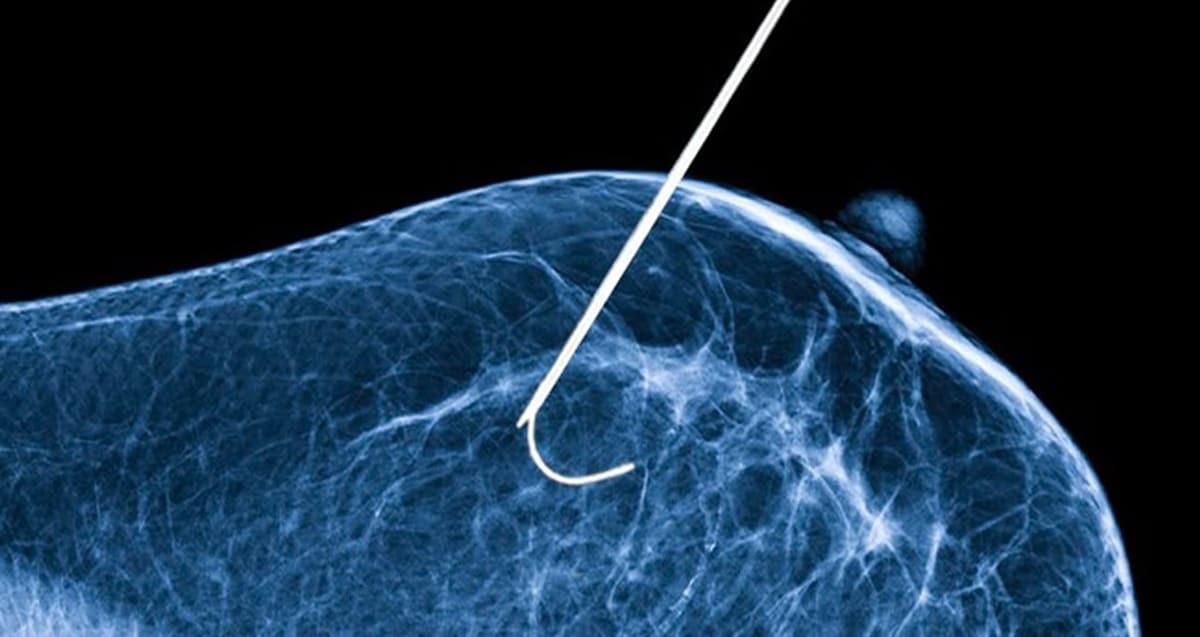

Na prática, crioablação é “matar” o tumor pelo frio. No protocolo testado pela Unifesp no Hospital São Paulo (HSP/Unifesp), o médico introduz uma agulha na lesão e injeta nitrogênio líquido a cerca de -140 °C, criando uma “bola” de gelo que destrói as células do tumor. No procedimento descrito pela equipe, foram feitos três ciclos de 10 minutos, alternando congelamento e descongelamento.

Além do número, o “como” também pesa. A própria Unifesp aponta que o procedimento pode ser feito em ambulatório, com anestesia local, sem necessidade de internação, e com incisão tão pequena quanto (ou menor que) a de uma biópsia.